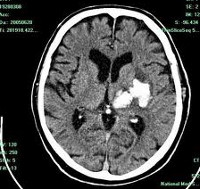

image

КТ головного мозга. Внутримозговые (интрапаренхиматозные) травматические гематомы с обеих сторон